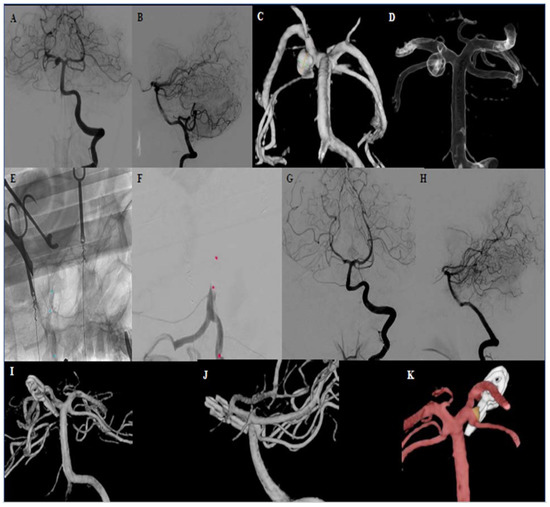

| 3 | 48 | Female | Proximal right side PCA aneurysm (P1 branch) Right SCA exits the P1 segment from the aneurysms side wall | 4 × 5 × 5 | no | Incidental finding Diagnostic in the context of a vestibular syndrome | N/A | N/A | 15 | 0 | 5 |

| 3 | 11 | 3 | Small remnant at the neck to preserve the SCA exit No aneurysm perfusion All branches open | ASCENT® 4 × 7 balloon (DePuy Synthes) | None |